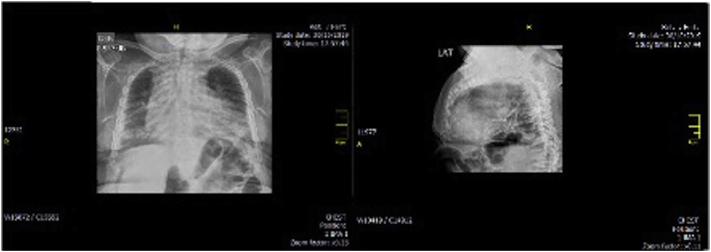

To present two female patients with Morquio A syndrome in their late adult years (over 50 years of age) with a classical phenotype, treated with enzyme replacement therapy; and to present a summary of the natural history and the characteristics of the disease, and the benefit of comprehensive management.

Enzyme replacement therapy with elosulfase alfa was effective, with an adequate safety profile in these two patients, showing evidence of sustained improvement in terms of endurance and gait patterns.

We present two cases of MPS IVA, with longer survival than reported previously in classical phenotypes associated with this disease condition. There is a paucity of reports of similar cases in the literature. We believe that the clinical heterogeneity of the disease manifesting with the classical phenotype, together with comprehensive management, have played a role in the survival of these two patients. Therapy with elosulfase alfa as part of comprehensive management has been crucial; we suspect a clinical response and infer a better quality of life and reduced burden for the caregiver, supporting its use in older patients.